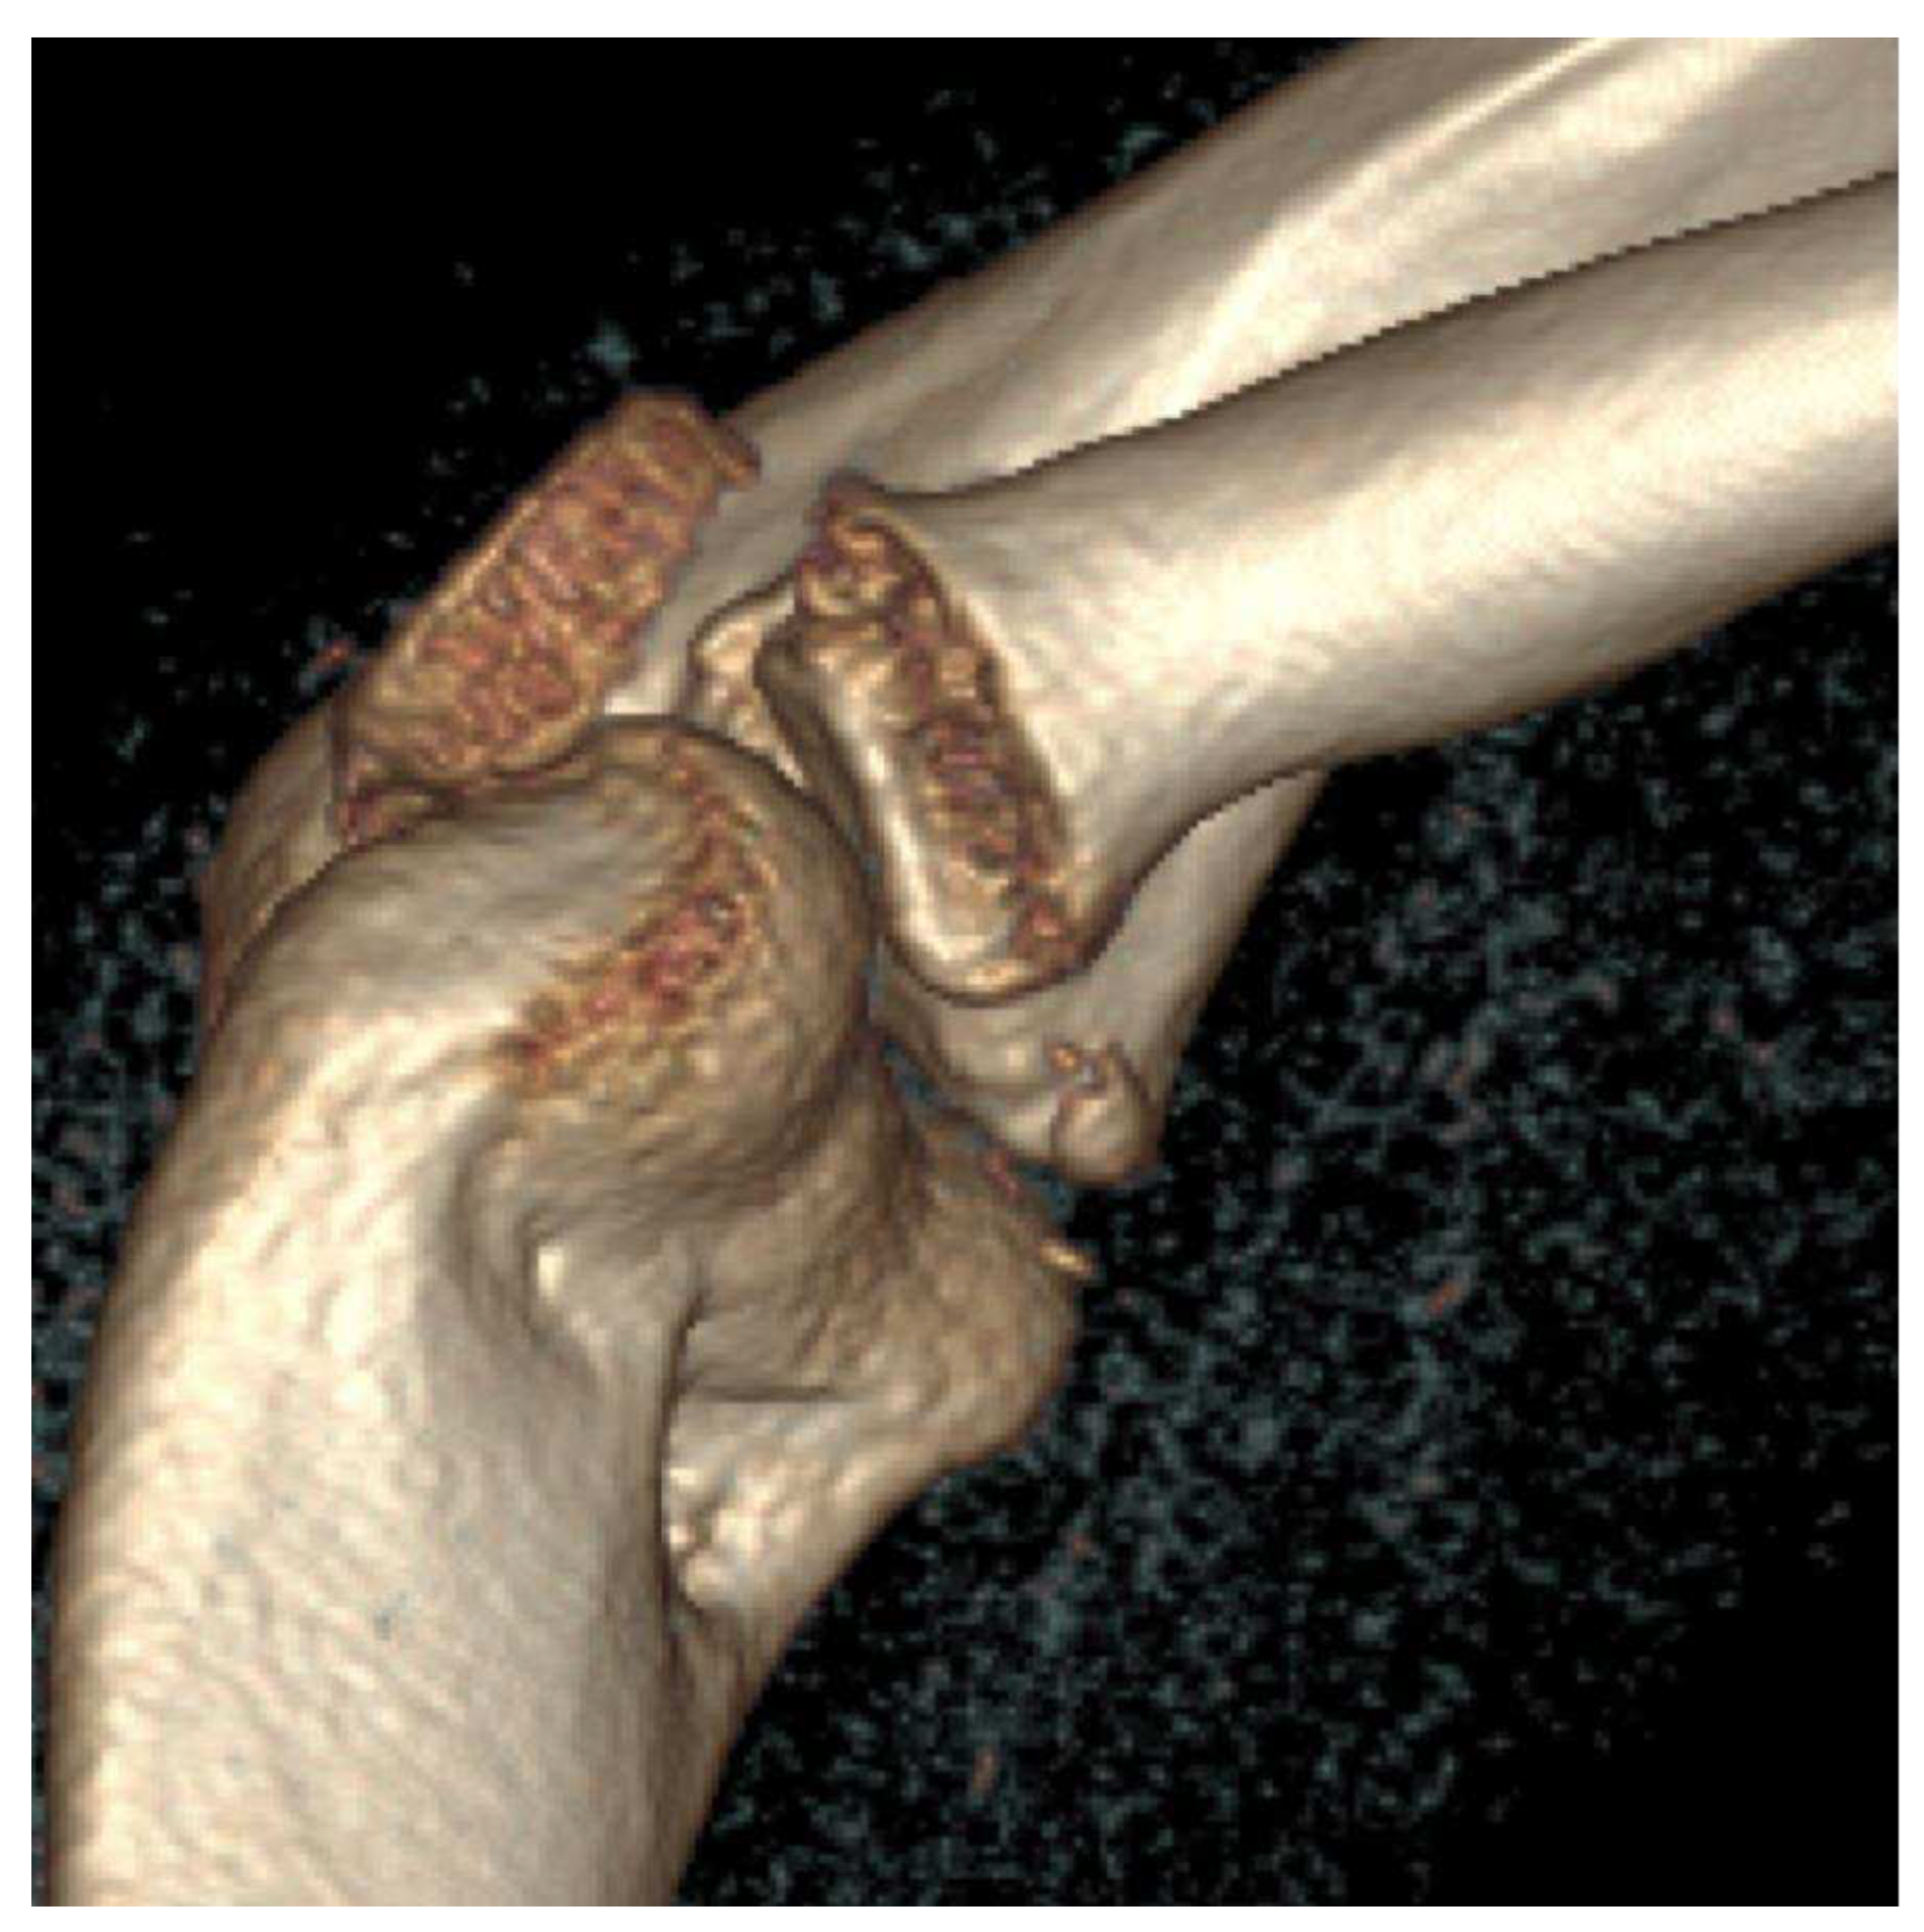

- Osteochondral fragment is displaced

- Joint effusion

- X-ray: Loose body, lucency